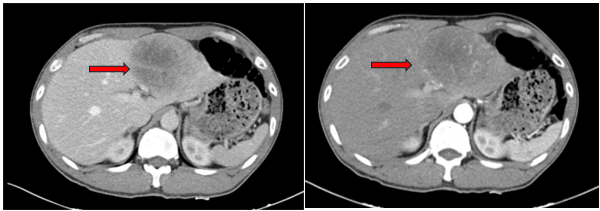

UNG THƯ BIỂU MÔ TẾ BÀO THẬN

Ung thư thận là loại ung thư thường gặp đứng thứ 14 trên toàn cầu, với hơn 430.000 ca mới được chẩn đoán vào năm 2020, và 434840 ca mắc trên toàn cầu vào năm 2022. Tỷ lệ mắc thay đổi theo khu vực địa lý, cao hơn ở châu Âu và Bắc Mỹ. Ung...